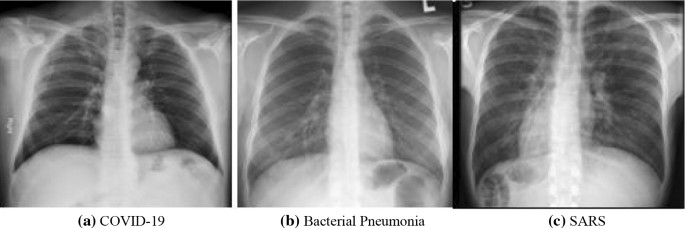

Sample Images From Covid Xray 5k Dataset The Images In The First Row Download Scientific Diagram